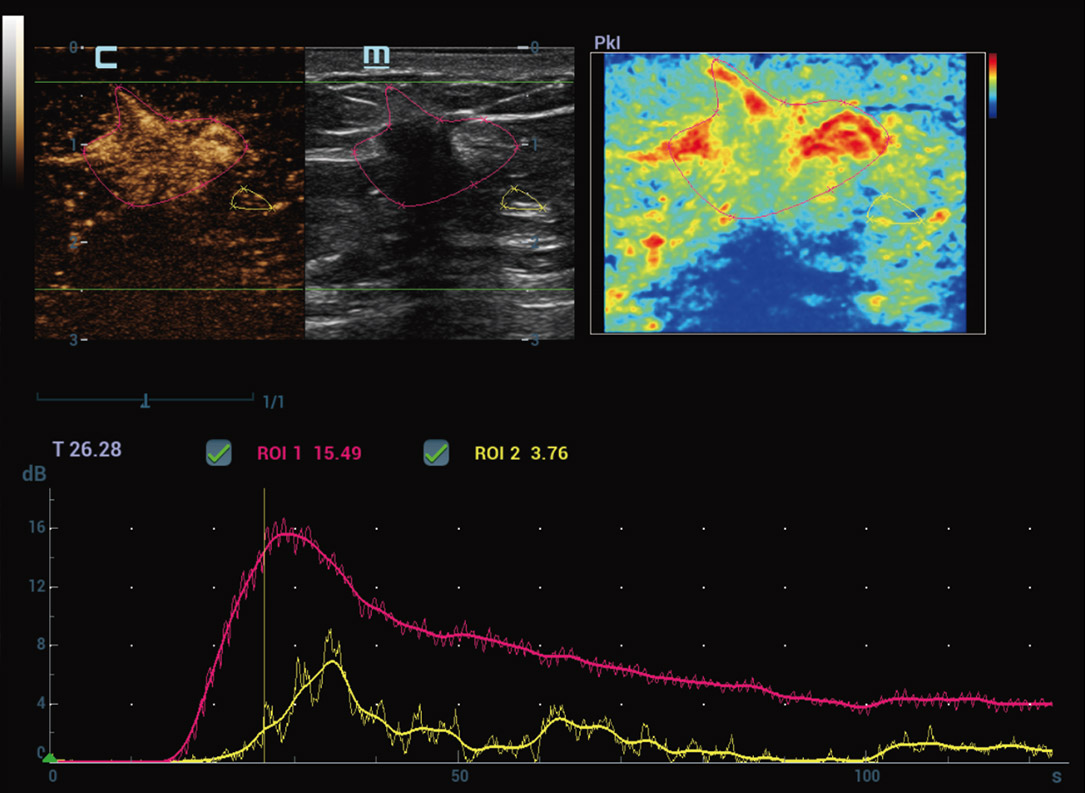

Nuova analisi quantitativa CEUS

Nuova QA CEUS tumore maligno al seno

La curva tempo-intensitĂ offre un'analisi quantitativa dell'imaging CEUS. La Nuova QA CEUS fornisce strumenti di analisi quantitativa all'avanguardia per la valutazione dei tumori e la ricerca clinica.

Strumenti di analisi multiparametrica M-Reference

M-Ref. C&E

M-Ref. C&E tumore maligno al seno

M-Ref. C&E supporta la visualizzazione del contrasto e della STE in un unico piano per una valutazione comparativa della perfusione e dell'elasticitĂ .